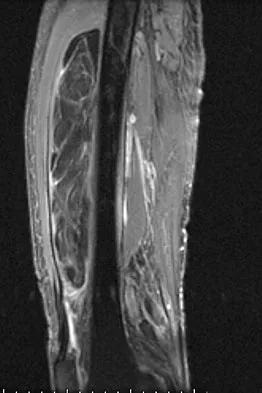

Figures 13a and 13b show the MRI scans of a 70-year-old patient who has a posterior calf mass. Examination reveals that the mass extends to the midcalf level. A biopsy specimen reveals a high-grade soft-tissue sarcoma. Metastatic work-up shows no lesions. Management should consist of

Explanation

Soft-tissue sarcomas generally are treated with radiation therapy and wide surgical resection. In this patient, involvement of most of the posterior calf compartment and circumferential involvement of the posterior tibial and peroneal neurovascular bundle makes limb salvage impractical. Any attempt at wide surgical resection would leave a poorly functioning limb with questionable surgical margins. A high below-knee amputation would be the best option. Radiation therapy alone is contraindicated. Lindberg RD, Martin RG, Romsdahl MM, et al: Conservative surgery and post-operative radiotherapy in 300 adults with soft tissue sarcoma. Cancer 1981;47:2391-2397. Sim FT, Frassica FS, Frassica DA: Soft tissue tumors: Diagnosis, evaluation, and management. J Am Acad Orthop Surg 1994;2:202-211.